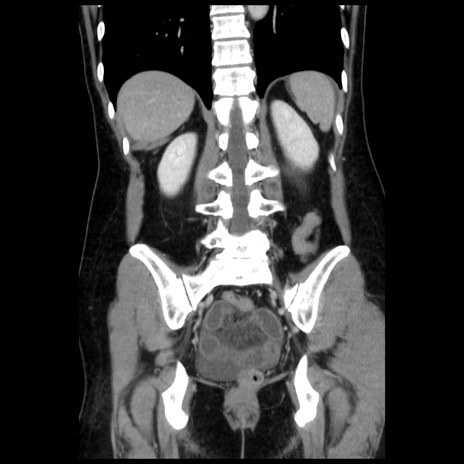

症例10(冠状断像)

【症例】 50歳代女性

【主訴】 腹痛

【現病歴】前日生レバーを食べた。今朝に排便あり。 昼前に突然発症の腹痛を生じ、当院救急外来を受診した。

【既往歴】 子宮筋腫にてで子宮全摘後

【身体所見】 意識清明、腹部:平坦、軟、下腹部やや左を中心に圧痛・反跳痛あり、筋性防御あり

【データ】WBC 7800、CRP 0.07